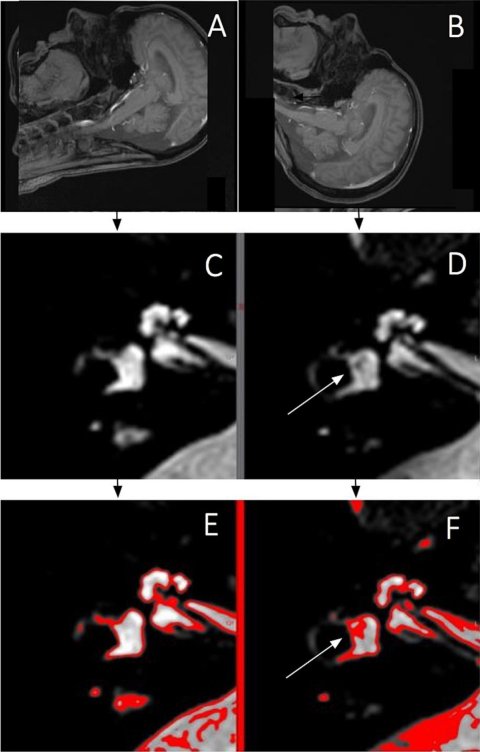

Bildquelle: Javor D, Leyer M, Ward BK et al., European Journal of Radiology 2026 (CC BY 4.0)

Hochfeld-MRT mit 3 Tesla und mehr ist in der Neuroradiologie mittlerweile Standard. Bei diesen Feldstärken kann das statische Magnetfeld mit winzigen elektrischen Strömen in den Innenohrflüssigkeiten wechselwirken. Die dabei entstehenden Lorentz-Kräfte sind dafür bekannt, Nystagmus (unkontrollierte, rhythmische Augenbewegungen) und Vertigo (Schwindel) bei Menschen mit intaktem Gleichgewichts-(Vestibular-)system auszulösen. Gleichzeitig reagieren MRT-Techniken, die das Labyrinth des Innenohrs abbilden, äußerst empfindlich auf langsame Flüssigkeitsbewegungen. Frühere Beobachtungen aus Krems hatten diese Effekte mit kleinen, scharf begrenzten, signalarmen Bereichen im Vestibulum in Verbindung gebracht, die keiner anatomischen Struktur entsprechen. Die neue Studie sollte nun prüfen, ob sich diese Hypointensitäten (als „flow voids“ bezeichnet) tatsächlich wie flussbedingte Artefakte verhalten und ob sie sich mit der Kopfneigung systematisch verändern.

Ein Team unter der gemeinsamen Leitung von Prof. Dr. Domagoj Javor, Leiter des Instituts für Diagnostische und Interventionelle Radiologie am Universitätsklinikum Krems (einem Lehr- und Forschungsstandort der KL Krems) sowie Dr. Béla Büki von der dortigen HNO-Abteilung, untersuchte 20 gesunde Erwachsene ohne bekannte vestibuläre Erkrankung in einem 3-Tesla-Scanner. Die Fallzahl wurde bewusst klein gehalten; die Autorinnen und Autoren verstehen das Projekt als Machbarkeitsstudie, nicht als abschließende klinische Prüfung. Bei jeder Person wurden zwei hochauflösende Innenohr-Scans mit einer T2-gewichteten SPACE-Sequenz durchgeführt: einmal mit nach vorne geneigtem Kopf (Kinn zur Brust) und einmal mit nach hinten geneigtem Kopf (Überstreckung). Rekonstruiert wurde in der Ebene des horizontalen Bogengangs. Zwei erfahrene Mediziner arbeiteten unabhängig voneinander und „verblindet” und bestimmten, welcher Anteil des Vestibulums von den signalarmen „flow-void“-Arealen eingenommen wurde.

Das Muster war eindeutig: Bei nach hinten geneigtem Kopf nahm die signalärmere Fläche im Vestibulum auf beiden Seiten im Mittel um rund 15 Prozentpunkte gegenüber der Kinn-zur-Brust-Position zu. In derselben Kopfposition berichteten drei der 20 Teilnehmenden – etwa 15% – über leichten Schwindel; bei nach vorne geneigtem Kopf trat dies nicht auf. „Unsere Befunde zeigen, dass diese kleinen dunklen Bereiche im Vestibulum keine fixen anatomischen Merkmale sind, sondern sich mit der Kopfposition im Magnetfeld verändern“, sagt Prof. Dr. Javor. „Genau das erwartet man bei einem gutartigen, positionsabhängigen Artefakt – aber nicht bei einer Innenohr-Pathologie.“

Für den klinischen Alltag schlagen die Autorinnen und Autoren einen pragmatischen Umgang vor: Wenn in einer T2-Spin-Echo-Sequenz eine verdächtige vestibuläre Hypointensität auffällt, kann es helfen, zu prüfen, ob sie sich mit der Kopfposition oder zwischen verschiedenen Sequenztypen verändert. Gradient-Echo-Sequenzen, die weniger empfindlich auf langsame Flüssigkeitsbewegungen reagieren, können als Vergleich dienen. Zudem kann es die Links-Rechts-Vergleichbarkeit verbessern, die Kopfneigung in sagittalen Übersichtsaufnahmen zu dokumentieren und konsequent in der Ebene des horizontalen Bogengangs zu rekonstruieren. „Radiologinnen und Radiologen sollten wissen, dass diese charakteristische, rautenförmige Hypointensität im Vestibulum bei Kopfüberstreckung tendenziell zunimmt und bei Kinn-zur-Brust-Position abnimmt“, sagt Dr. Béla Büki. „Isoliert betrachtet kann sie wie eine fokale Läsion wirken – in vielen Fällen spiegelt sie jedoch lediglich Flüssigkeitsbewegung im starken Magnetfeld wider.“